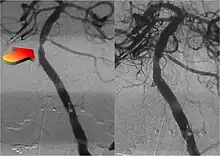

Parallel to the development of catheters, in the radiology and neuroradiology units, image technology dramatically improved: Charles Mistretta in 1979 invented digital subtraction angiography (DSA), the technique currently in use. It consists of performing skull radiography under basic conditions which are then "subtracted" to the image after contrast media injection, to provide an image where only brain vessels are displayed, with great improvement in the diagnostic potential.

Between the end of the 1980s and the beginning of the '90s, INR was suddenly revolutionized after the work of two Italian physicians: Cesare Gianturco and Guido Guglielmi. The first combined a deep knowledge of diagnostic radiology with a great ability to solve technical and manual problems. He invented Gianturco's coils, which he used to make the first attempts to embolize arteries and aneurysms.[8] Gianturco also patented the first endovascular stent approved by the American FDA;[8] a device with a great legacy. In the second half of the 1980s, Sadek Hilal was the first in Columbia University to use coils to treat brain aneurysms; but this technique was inaccurate and dangerous because the coils were released with little control with great risk of occluding the vessel from which the aneurysm originated (parent vessel).[9] The coil embolization was revolutionized by the work of Guido Guglielmi in UCLA, who realized that electricity could function as a controlled release mechanism for coils; in 1991 he published two works dealing with the embolization of brain aneurysms by means of detachable platinum coils[10] (Guglielmi's coils). The treatment of aneurysms was thus made more accessible and safe.